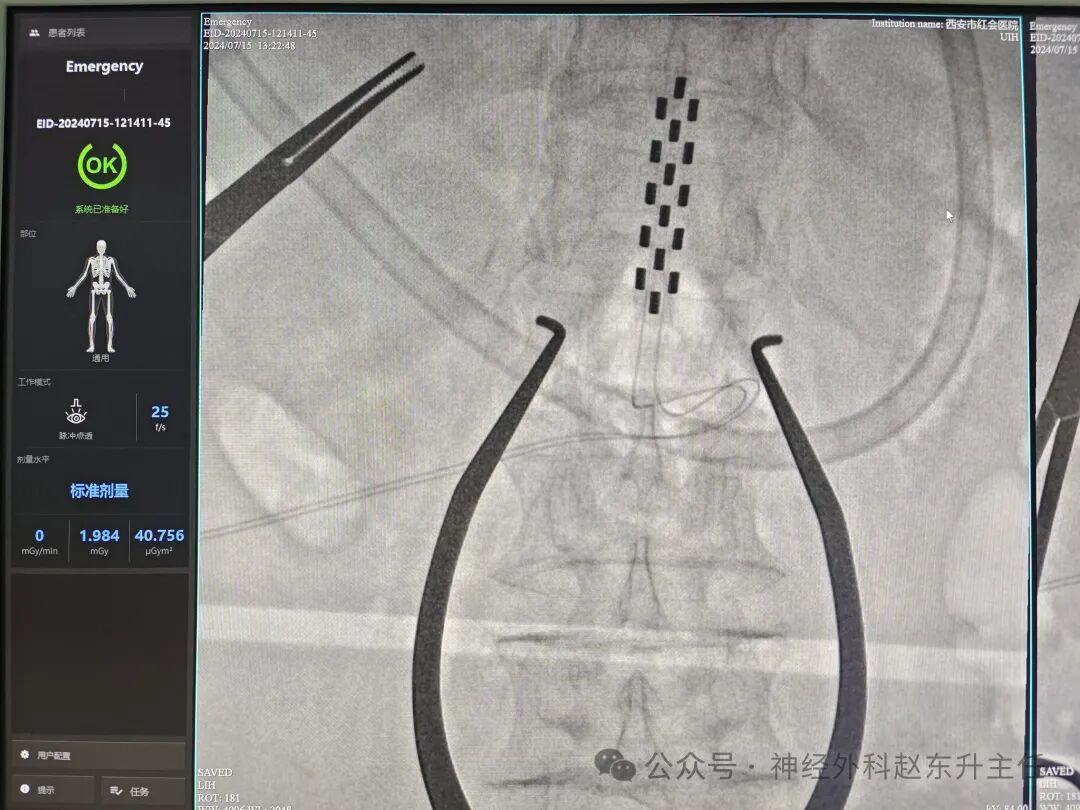

SCS需分两期完成,全程在影像引导下进行:

1. 一期(测试期):

- 电极植入:局麻下经皮穿刺或小切口,将柱状/片状电极置入目标脊髓节段硬膜外腔(如颈髓C2-C4用于促醒,胸腰段T19-L1用于疼痛)。

- 临时外挂刺激器:连接体外电池,测试7-14天,调整参数(频率1-100Hz、脉宽100-500μs)观察疗效。

脊髓电刺激术通过精准的神经调控,在疼痛缓解和功能恢复中展现显著优势,尤其适用于传统治疗无效的慢性疾病。其成功依赖于严格的适应症筛选、规范的手术操作及长期随访管理。未来随着电极微型化、无线充电技术的发展,SCS的微创性和可逆性将进一步提升,拓展至更多神经系统疾病的治疗领域。西安市红会医院神经外科赵东升主任在此类手术方面积累了大量临床经验。

IMG_20240715_131940.jpg  赵东升主任简介

医学硕士,主任医师,从事神经外科近20年,曾长期在第四军医大学西京医院神经外科工作。使用独创的“三维一体疗法”成功促醒大量昏迷病人,使上百例脊髓损伤瘫痪患者重新站起来。在西安市红会医院完成院内第一例脊髓电刺激治疗昏迷病人,第一例脊髓电刺激手术治疗截瘫病人,第一例脊髓电刺激手术治疗下肢缺血顽固性疼痛。主编专著3部,参编专著11部,发表学术论文30余篇,荣获国家专利32项(其中四项发明专利),担任多部杂志编委及审稿专家。